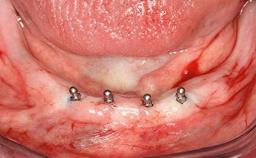

A 93-year-old female patient presented in September 2010 with an enlarged swelling on the lingual side of her lower incisors. At the time, she was essentially healthy, except for reduced vision due to bilateral age-related macular degeneration. She had been a heavy smoker (about 30 cigarettes a day) for the past 20 years after becoming a widow. The patient lived at home by herself, with full-time domestic support. An extraoral examination revealed nothing adverse. Intraoral plaque control was anything but ideal, and a soft-tissue tumescence was visible around the lingual aspect of 41–42. Because the nature of the lesion was not clear, a biopsy was carried out that revealed the inflammatory nature of the lesion. The panoramic radiograph showed six irregularly distributed mandibular implants supporting a full-arch prosthesis, with various degrees of interproximal peri-implant resorption. The periapical radiograph revealed interproximal bone resorption mesially and distally to implant 41.

# of Teeth 6

# of Implants 2

Type of Implants One-Piece